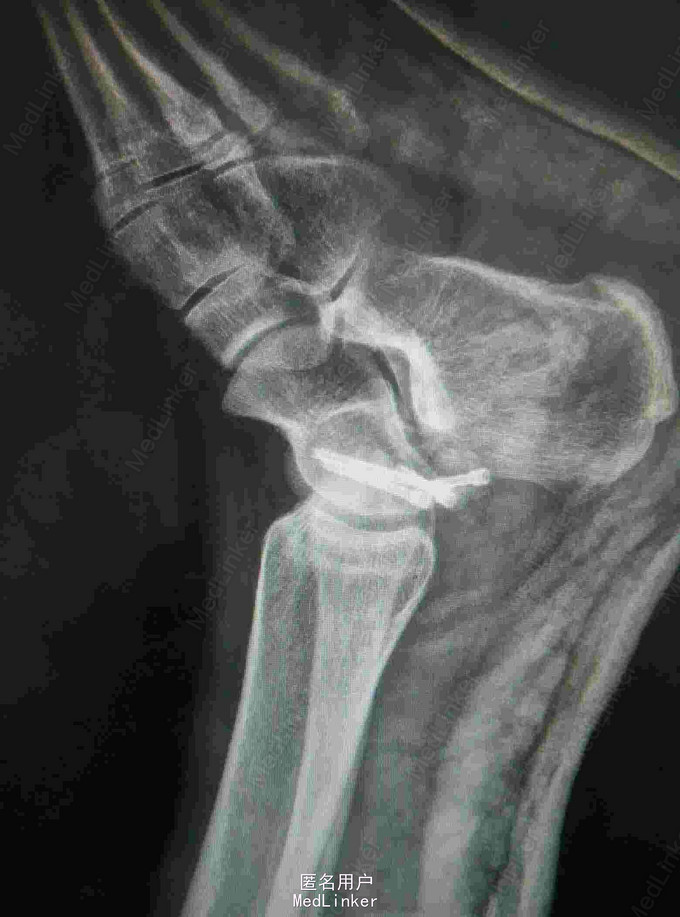

查体:左踝关节肿胀明显,局部皮肤压痛,无皮损及皮下淤斑,踝关节活动受限,各足趾感觉正常,足背动脉搏动存在。 辅查:我院CT提示距骨、足舟骨、跟骨骨折

诊断:左足距骨、足舟骨、跟骨骨折 治疗:距骨骨折切开复位内固定术

随访:石膏固定4-6周,3月内禁止负重,定期复查。 讨论:患者X线片对左足骨折显示不够清楚,基本常规行CT,可以看到明显的距骨骨折,累及关节面,需手术复位关节面。足舟骨以及跟骨骨折未明显移位保守处理。